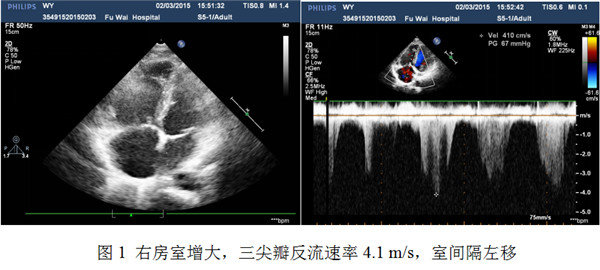

3个月后患者如约来院随访,查血浆蛋白S活性29%,血浆蛋白C活性恢复正常,抗凝血酶III活性正常,确诊蛋白S缺乏症。复查D-二聚体575 ng/ml,肺动脉CTA示双肺动脉各叶段多发充盈缺损。肺灌注显像示双肺多发性肺段性血流灌注受损,与3月前肺灌注显像比较无明显改变。超声心动图示右房室增大,较3月前有所回缩,右室壁增厚,TAPSE 20 mm,三尖瓣反流速率4.1 m/s,左室内径大致正常,室间隔左移(图1)。